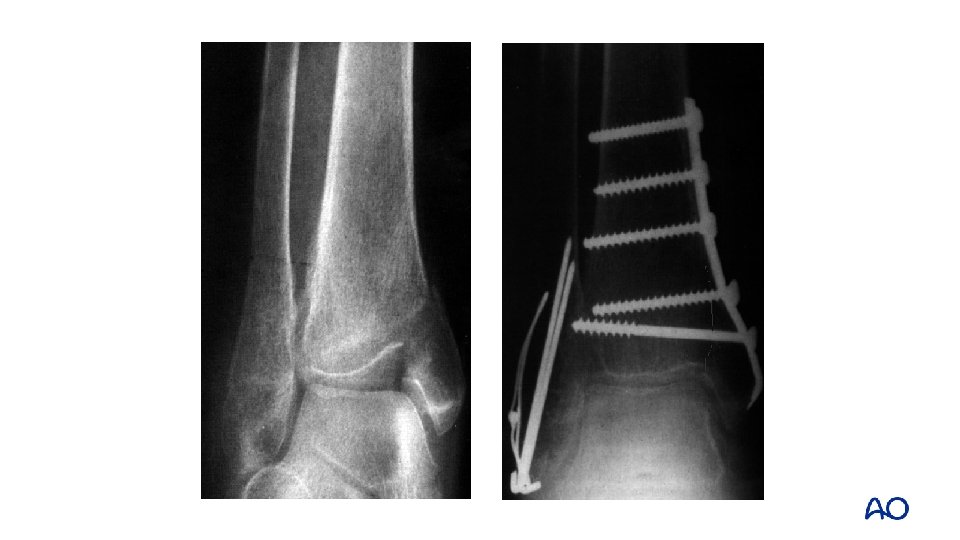

Weber A—medial malleolar fixation • Vertical shear injury • Always inspect joint • Restore and bone graft marginal impaction • Screws perpendicular to fracture plane • NOT from tip—malreduction • Buttress plate adds stability (antiglide) • 3. 5 screws better than “malleolar”

Vertical medial malleolar fracture